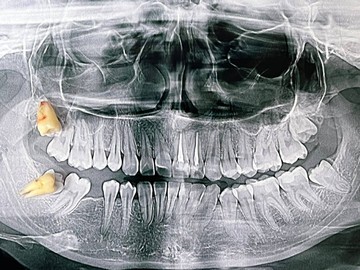

Атравматичное удаление зубов – наиболее безболезненная и щадящая процедура, которая практически не травмирует десну и костную ткань.

Зуб извлекается частями, что позволяет не травмировать окружающие ткани.

В нашей клинике осуществляется удаление самых сложных «зубов мудрости». Обычно удаление зуба под местной анестезией занимает от 10-15 минут, но иногда процедура может занять 30 или даже 60 минут и более.